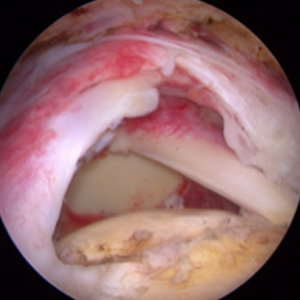

「腱板断裂」の形態は様々です 腱板完全断裂 関節内まで全層にわたって切れているものを完全断裂または全層断裂と呼びます。下図のように、そのサイズも大小様々です。 小断裂 中~大断裂 腱板不全断裂 一方、腱板の表(おもて)側や裏(うら)側だけが部分的に切れる「腱板不全断裂」もあります。 表層断裂 腱の表面がめくれた状態 深層断裂 関節の内面が裂けた状態

整形外科における手術の役割 肩腱板断裂治療のアルゴリズム 不全断裂 小断裂 中~大断裂 一次修復不能広汎性断裂 保存療法(リハビリ:運動療法/物理療法) 手術療法 関節鏡下腱板修復術 腱移行術、腱移植術、リバース型人工関節 腱板断裂の治療の基本は保存療法ですが、それが反応しない場合には、関節鏡下腱板修復術が適応されます。 修復前 修復後 関節鏡下腱板修復術は「肩に小さな穴を数か所開け、関節鏡で中をのぞきながら縫い合わせる方法」で、私の得意分野です。 不全断裂 小断裂 中~大断裂 一次修復不能広汎性断裂 保存療法(リハビリ:運動療法/物理療法) 手術療法 関節鏡下腱板修復術 腱移行術、腱移植術、リバース型人工関節 縫いきれないほどの大きな断裂には、腱の移植や人工関節が必要になります。 手術を望まない方へは、間葉系幹細胞を用いた再生医療の提供に取り組んでいます。